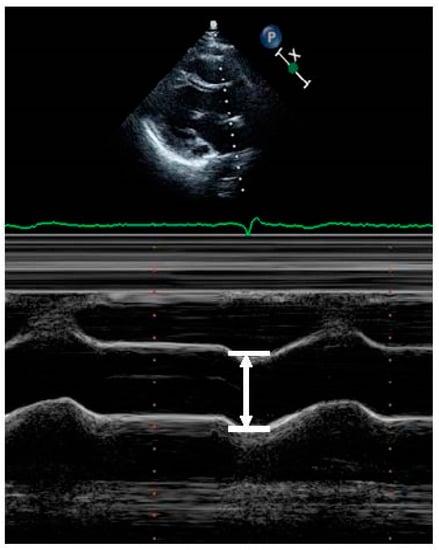

| II | Aortic root diameter (mm) | 34.94 ± 4.18 | 32.66 ± 3.99 | <0.001 |